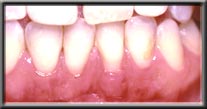

With the wear and tear of time, even normal attached gum can be worn away, generally from vigorous brushing. This often happens in people with naturally thin tissues, or when the tissues have been stretched during orthodontics. If there is still adequate attached gum to act as a barrier to the muscle, the treatment for recession is to ensure further damage isn't done when brushing. However, if the attached gum is worn to the point where it cannot resist the constant pull of the mucosa, recession will continue unless a new hard band of gum is placed. Unchecked, the recession can cause tooth loss as the bone recedes with the tissue and tooth support weakens.